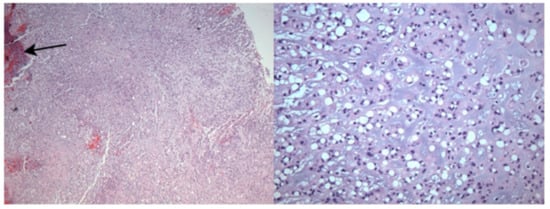

5.2. Histopathology